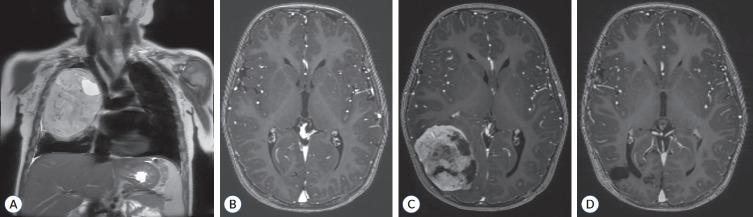

Pathogenic germline variants (PGVs) are increasingly recognized as critical elements in pediatric cancer predisposition. Determining the pathogenicity of germline variants is a dynamic process, with advancements in next-generation sequencing and expanding genome databases reshaping our understanding of cancer genomics. This article reviews the role of PGVs in key oncogenic pathways, including RTK (receptor tyrosine kinase)/RAS/MAPK (mitogen-activated protein kinase), PI3K (phosphatidylinositol 3-kinase)/AKT (v-akt murine thymoma viral oncogene homolog 1), WNT (wingless-type), and Hedgehog signaling, highlighting their associations with specific cancer predisposition syndromes and neurosurgical implications. Most PGVs are inherited in an autosomal dominant pattern and are frequent in tumor suppressor genes, while autosomal recessive conditions like Ataxia-telangiectasia and Fanconi anemia are less common. Germline variants in proto-oncogenes such as PTPN11, KRAS, and HRAS are associated with RASopathies, including Noonan and Costello syndromes, which show variable cancer risks. Similarly, PTEN PGVs, linked to Cowden syndrome, and DICER1 PGVs, responsible for DICER1 syndrome, exemplify the diverse clinical presentations and risks of pediatric cancer predisposition syndromes. Medulloblastoma, a pediatric-specific brain tumor, shows an increasing proportion of PGVs, with approximately 12% of all medulloblastomas harboring PGVs in APC, PTCH1, SUFU, and ELP1 in the WNT-activated and sonic hedgehog-activated subtypes. Emerging evidence suggests that approximately 8.5-20% of pediatric cancer patients harbor PGVs, with a substantial proportion arising de novo. Routine germline screening for pediatric cancer patients is increasingly recommended, as many PGVs lack family history. Programs like STREAM (Solid Tumor REsearch And Magic) in Korea underscore the importance of comprehensive pediatric genome databases for personalized precision medicine. As neurosurgeons are frequently the first to encounter central nervous system tumor manifestations, a robust understanding of genomic medicine is essential. This review emphasizes the need for international collaboration to develop actionable insights into pediatric cancer genomics, ultimately improving diagnostic, therapeutic, and preventive strategies.

致病性种系变异(PGVs)日益被认为是儿童癌症易感性的关键因素。确定种系变异的致病性是一个动态过程,随着下一代测序技术的进步和基因组数据库的不断扩展,我们对癌症基因组学的理解也在不断重塑。本文综述了PGVs在关键致癌途径中的作用,包括RTK(受体酪氨酸激酶)/RAS/MAPK(丝裂原活化蛋白激酶)、PI3K(磷脂酰肌醇3激酶)/AKT(v-akt小鼠胸腺瘤病毒癌基因同源物1)、WNT(无翅型)和Hedgehog信号通路,强调了它们与特定癌症易感性综合征的关联以及神经外科意义。大多数PGVs以常染色体显性模式遗传,在肿瘤抑制基因中较为常见,而像共济失调毛细血管扩张症和范可尼贫血等常染色体隐性疾病则较少见。原癌基因中的种系变异,如PTPN11、KRAS和HRAS,与RASopathies相关,包括努南综合征和科斯特洛综合征,这些综合征表现出不同的癌症风险。同样,与考登综合征相关的PTEN PGVs和导致DICER1综合征的DICER1 PGVs,体现了儿童癌症易感性综合征的多样临床表现和风险。髓母细胞瘤是一种儿童特有的脑肿瘤,PGVs的比例越来越高,在WNT激活型和音猬因子激活型亚型的所有髓母细胞瘤中,约12%在APC、PTCH1、SUFU和ELP1中存在PGVs。新出现的证据表明,约8.5%-20%的儿童癌症患者携带PGVs,其中很大一部分是新发的。由于许多PGVs缺乏家族史,越来越多的人建议对儿童癌症患者进行常规种系筛查。韩国的STREAM(实体瘤研究与魔法)等项目强调了全面的儿童基因组数据库对个性化精准医学的重要性。由于神经外科医生常常是首先遇到中枢神经系统肿瘤表现的人,因此对基因组医学有深入的了解至关重要。本综述强调了开展国际合作以深入了解儿童癌症基因组学从而最终改善诊断、治疗和预防策略的必要性。